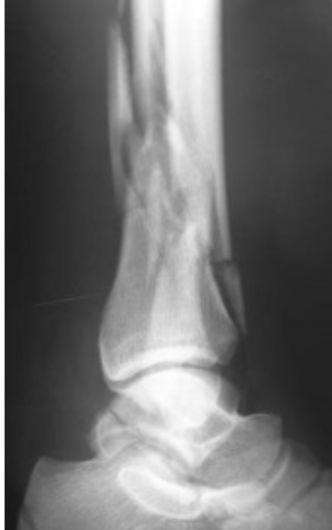

Subluxation

ess than 100% but greater

than 0% apposition between two bone at the

joint level